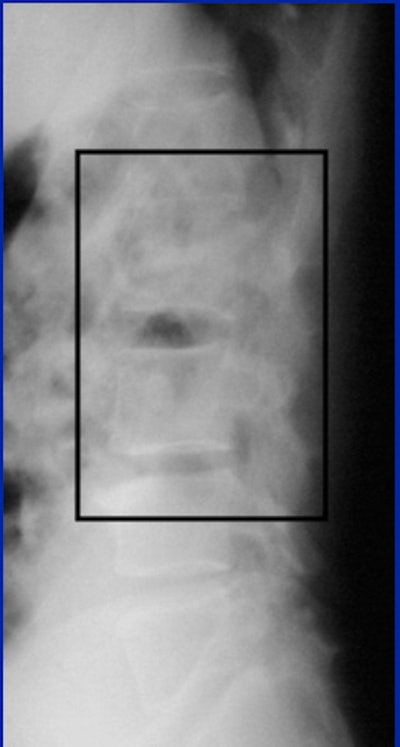

Image C

"With CT, you see that it's not just a compression fracture of the superior endplate, but really it's a burst fracture involving the anterior, middle, and posterior columns. The fracture goes through the vertebral body (with) retropulsion of bone, and it goes through the spinous process, through the lamina, and even into the facet joint."